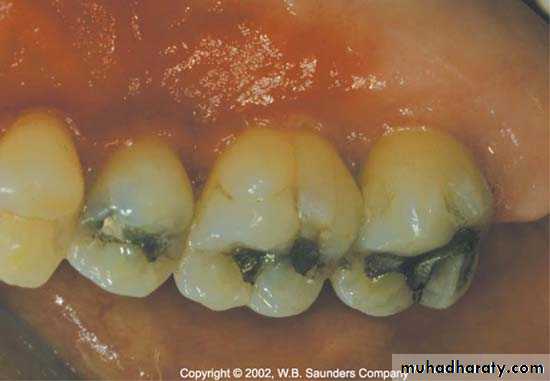

Materials

Restorative materials not injurious to tissue except cold cure acrylic.Its provide rough surface ,If its not polished well & accessible to cleaning.

The materials could be classified according to its smoothness from the smoother one which is ceramic ,gold, amalgum, composite, acrylic.

More importantly, tissues respond more to the differences in surface roughness of the material rather than the composition of the materials themselves.

The rougher the surface of the restoration subgingivally, the greater the plaque accumulation and gingival inflammation.

In clinical research,porcelain,highly polished gold, and highly polished resin all show similar plaque accumulation.

Regardless of the restorative material selected, a smooth surface is essential on all materials which are subgingivally placed.